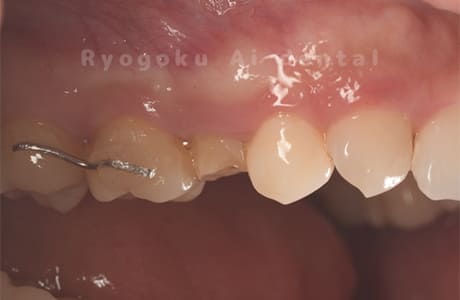

Case04

-

- 原因

- 重度カリエス、C3急化Pul

- 治療期間

- 約6ヶ月

- 治療内容

- 部分矯正、クラウンレングスニング、セラミッククラウン

- 治療費用

- 約350,000円

他院での説明で抜歯した後にインプラント治療を提案された患者さんです。虫歯が大きく、被せるための歯の長さが足りないため、埋まっている歯牙を引っ張り上げ、セラミックで被せたケースです。歯牙の状態も良好で、問題なく経過しています。